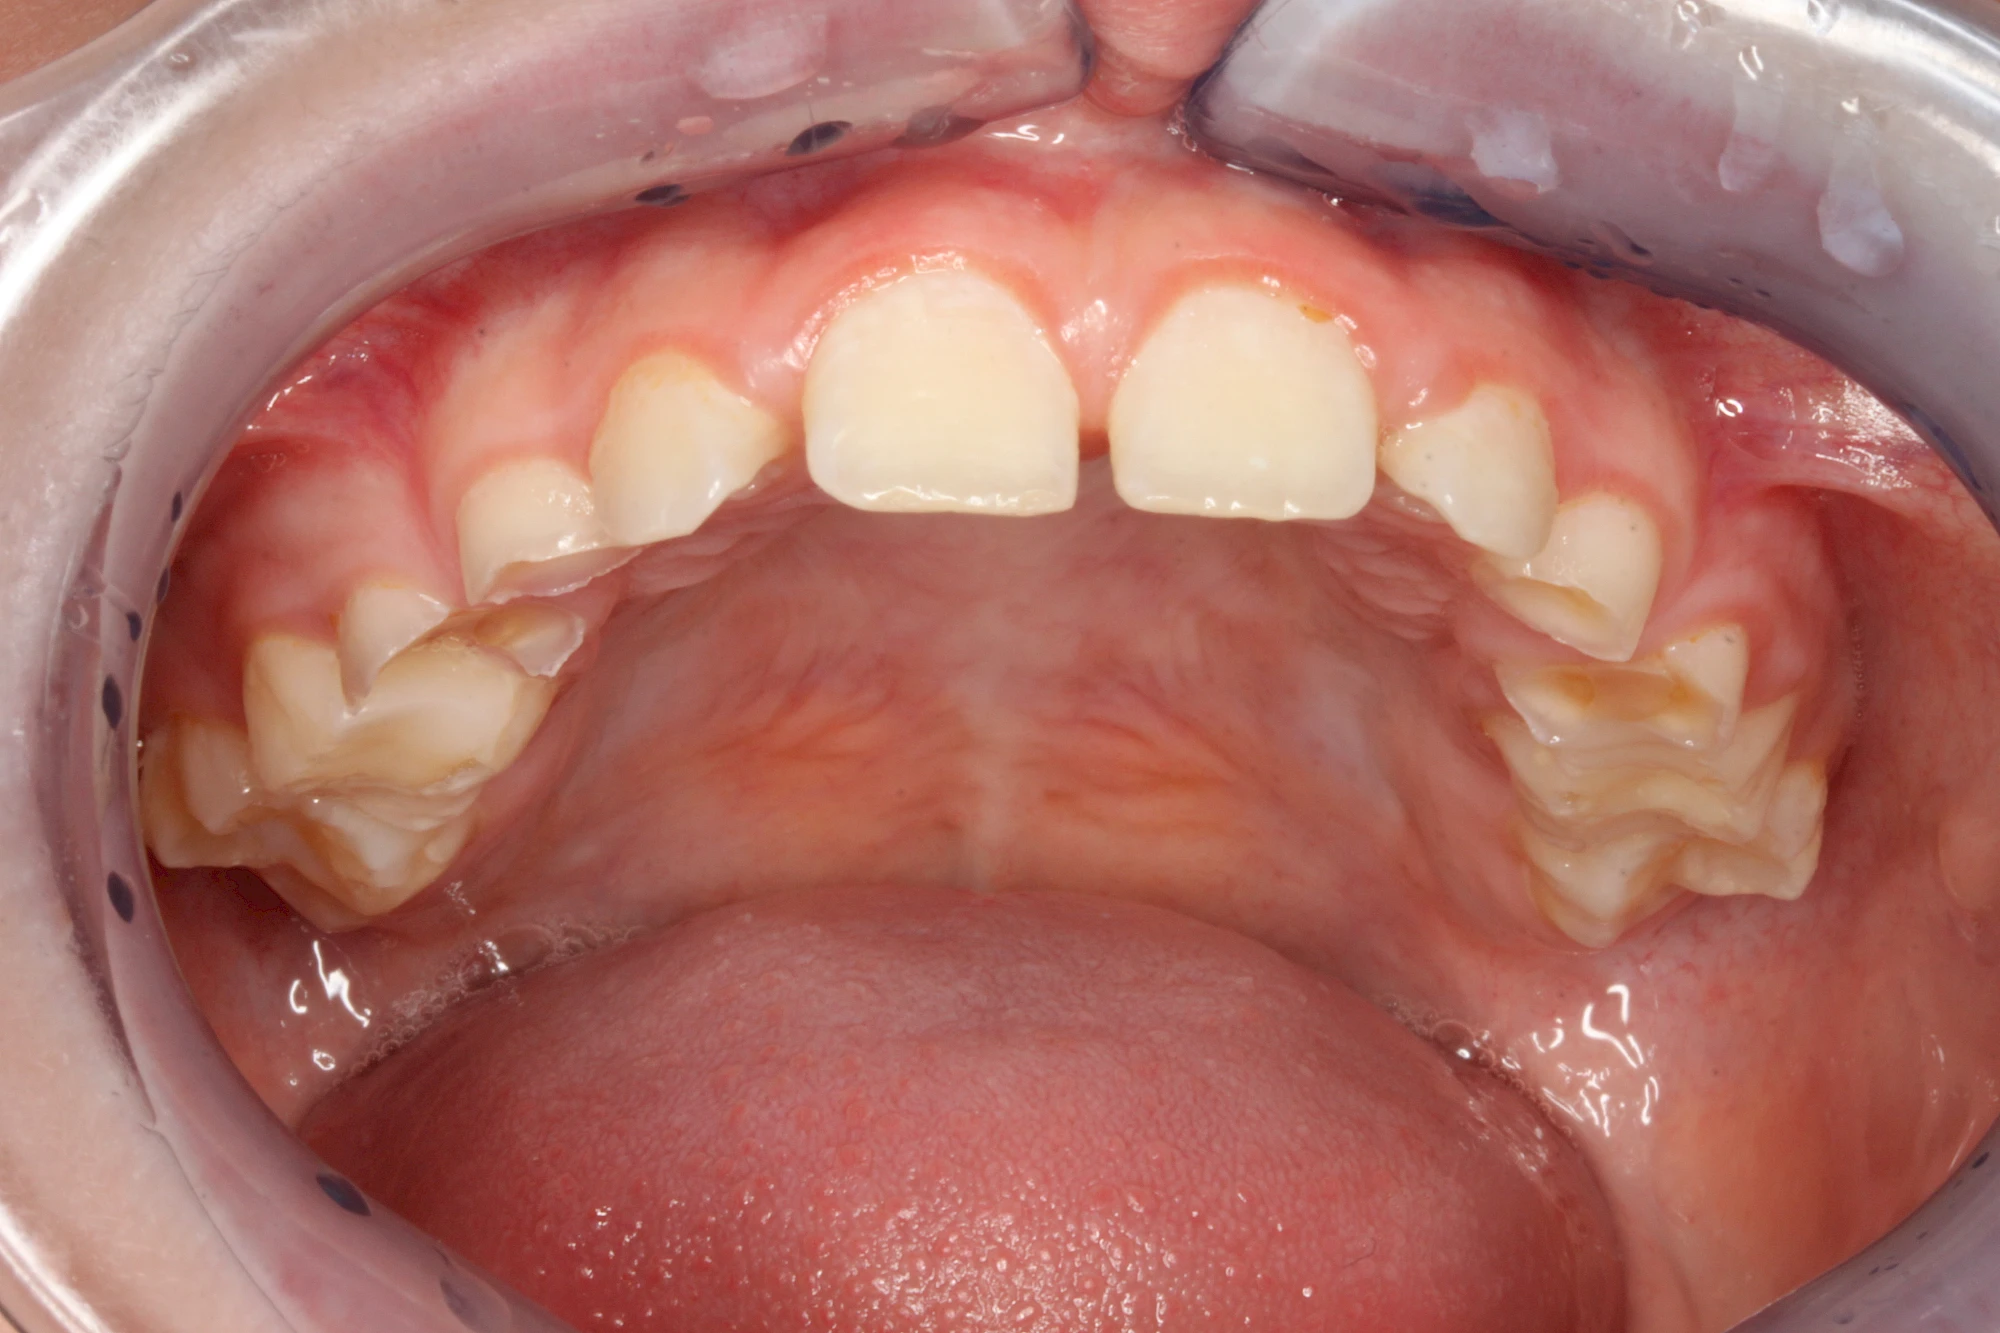

Über die Zeit können verschiedene Prozesse die Zahnhartsubstanzen aufzehren:

- Abnutzung durch Kauen (Abrasion) oder duch durch übermäßiges Knirschen bzw. Pressen (Attrition)

- Säurebedingte Auswaschung (Erosion)

Auswaschung (Erosion) dagegen ist eine Verschleißerscheinung der Zähne aufgrund von immer wiederkehrenden Säureangriffen durch die Nahrung, verstärkt zum Beispiel durch den Genuss säurehaltiger Getränke oder Speisen. Auch bei Menschen mit einer Essstörung (z. B. Bulimie) können die Zähne durch die Magensäure ausgewaschen erscheinen.

Eine Sonderform sind sogenannte keilförmige Defekte im Bereich der Zahnhälse. Hier geht man davon aus, dass Knirschen und Pressen in Kombination mit falschen Putzgewohnheiten (zu hoher Putzdruck, Verwendung von Zahnpasta mit hohen Abrasionswerten) eine Rolle spielen.